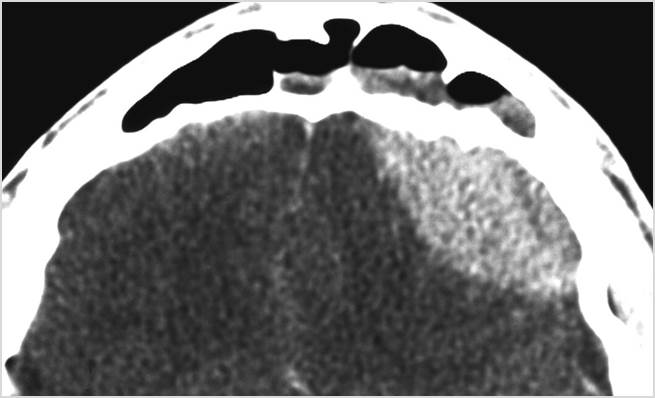

There is brain edema specifically involving the frontal and temporal lobes.

There is cerebritis specifically involving the frontal and temporal lobes.

There is brain abscess specifically involving the frontal and temporal lobes.